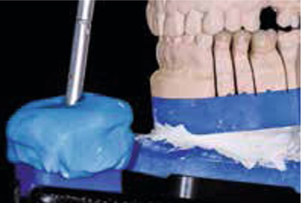

In de tijdelijke fase begonnen we met het vervaardigen van een mock-up in het front om de lengte van de nieuw frontelementen te bepalen (afbeelding 16 ). Tevens voerden we een esthetische facebow en beetbepalingen uit. Ook werden de esthetische en fonetische checklists ingevuld. Hiervoor gebruikten we de lijsten zoals die zijn opgesteld door Mauro Fradeani. Deze lijsten worden bij zijn boek The esthetic rehabilitation in fixed prosthodontics - vol 1 geleverd. Al deze informatie werd, samen met de overige informatie uit de aanvullende onderzoeken en met een paar nauwkeurige afdrukken (Impregum, 3M Espe) aan de tandtechnicus gegeven voor het vervaardigen van een set-up in was (afbeelding 17 en 18 ) en de bijbehorende mallen.

Afb. 21

De putty mal, gemaakt aan de hand van de set-up in was, is gevuld met chemisch uithardende kunsthars. Na etsen en het aanbrengen van bonding op de ongeprepareerde elementen wordt deze mal geplaatst. Uitharding wordt afgewacht en overmaat kan eenvoudig worden verwijderd.